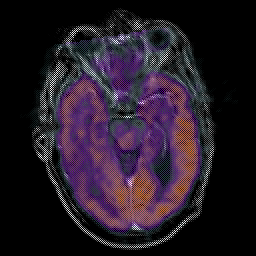

Glioma Overlay -- Slice #8

[Home][Help][Clinical] Slice 8